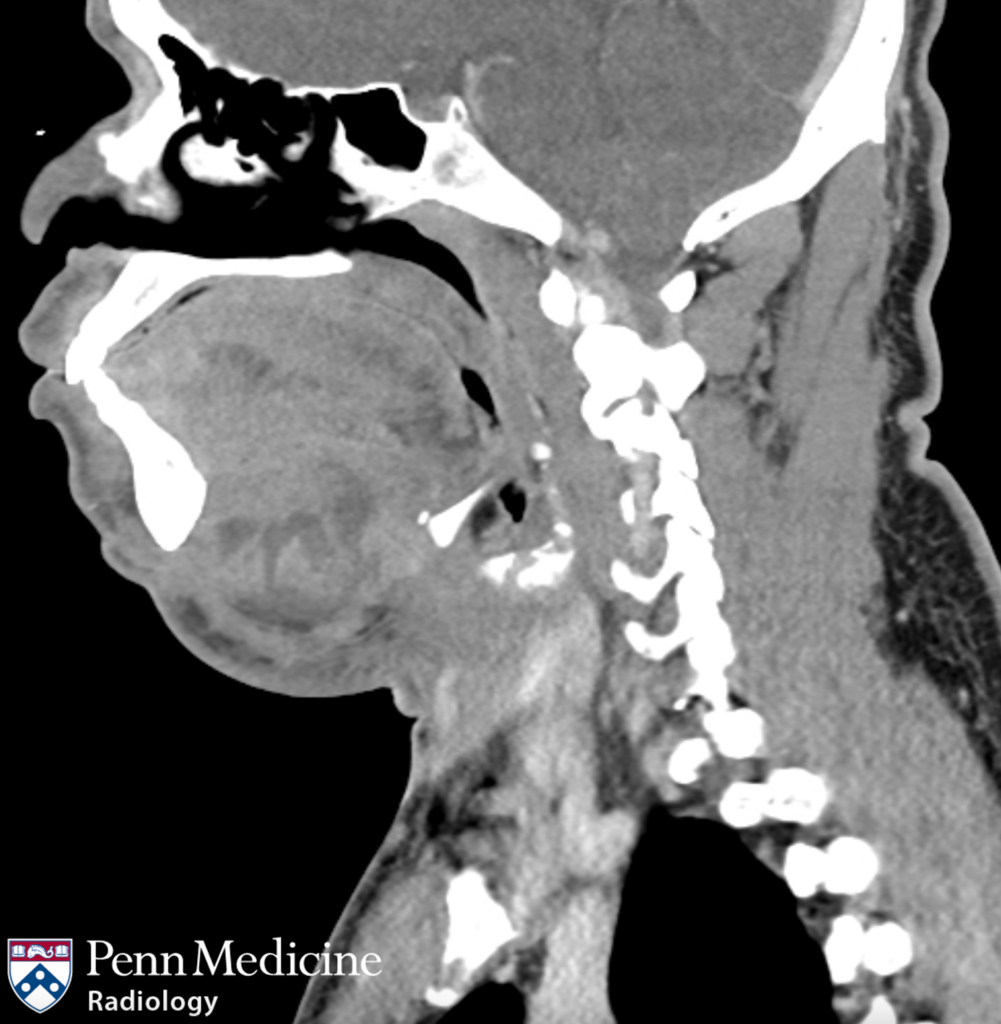

A 38-year-old man with four days of lower jaw pain and swelling.

66-year-old man with asymmetrical facial appearance